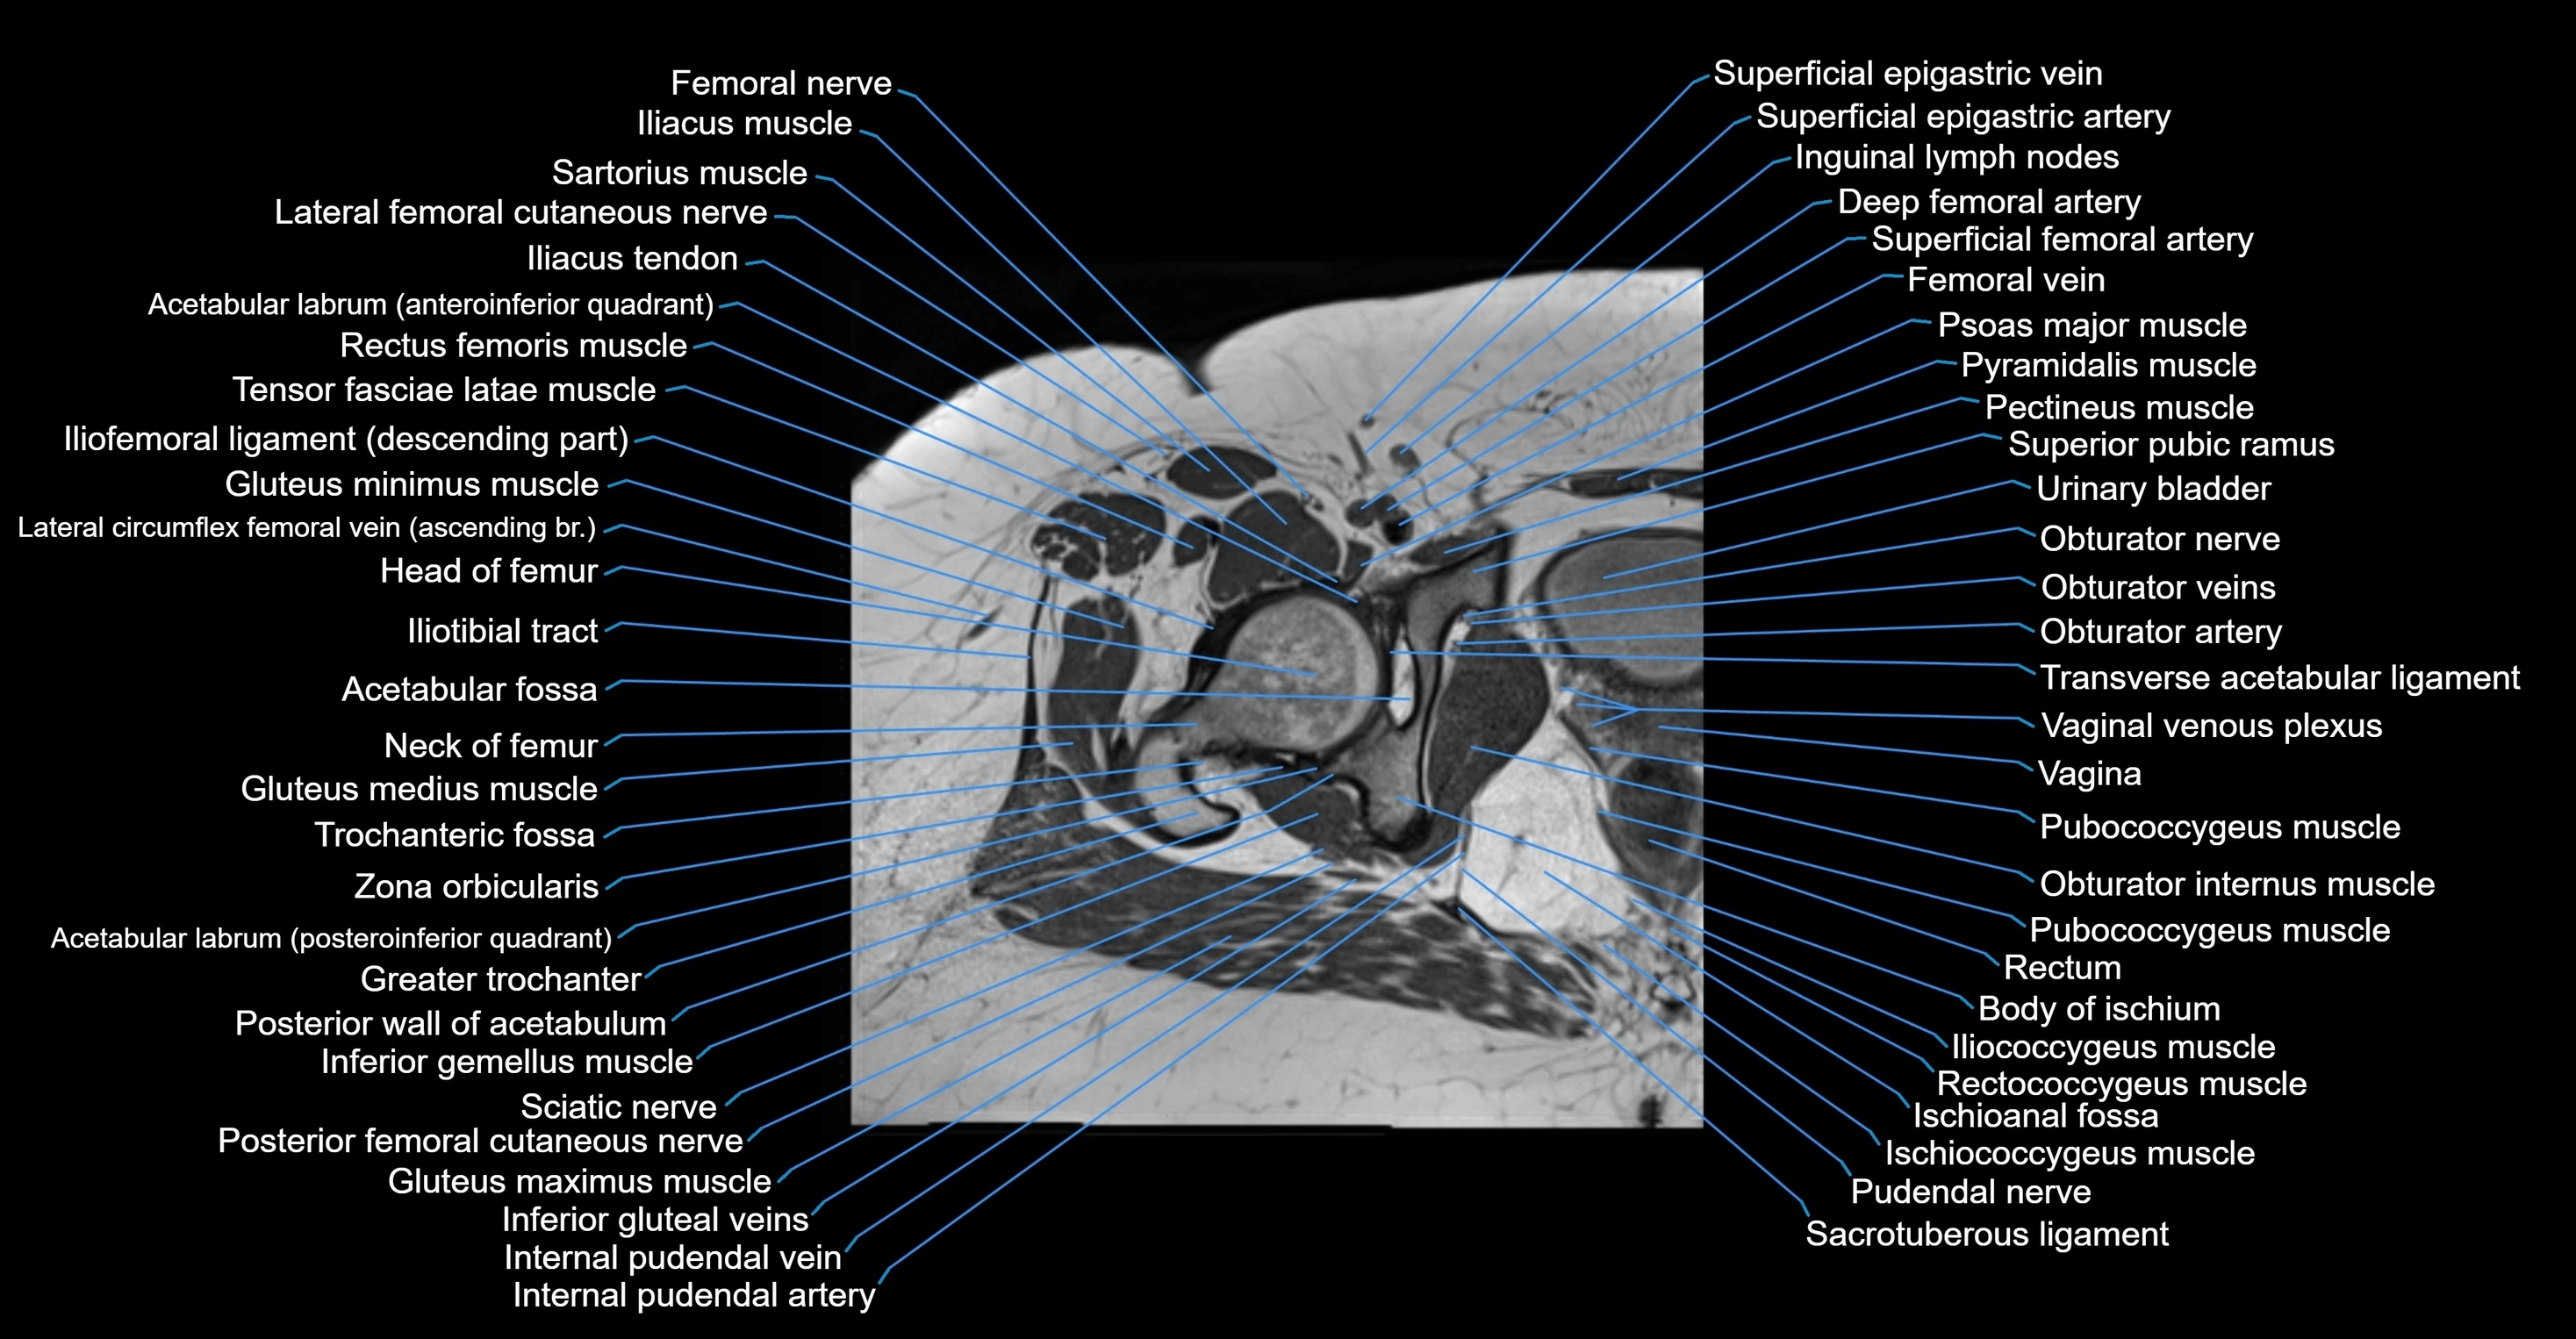

- Body of ischium

- Deep femoral artery (profunda femoris)

- Femoral nerve

- Femoral vein

- Gluteus maximus muscle

- Gluteus medius muscle

- Gluteus minimus muscle

- Greater trochanter

- Head of femur

- Iliococcygeus muscle

- Iliotibial tract

- Inferior gemellus muscle

- Inguinal lymph nodes

- Ischiococcygeus muscle

- Neck of femur

- Obturator artery

- Obturator internus muscle

- Obturator nerve

- Obturator veins

- Pectineus muscle

- Psoas major muscle

- Pubococcygeus muscle

- Pudendal nerve

- Pyramidal muscle (pyramidalis muscle)

- Rectum

- Rectus femoris muscle

- Sacrotuberous ligament

- Superior pubic ramus

- Tensor fasciae latae muscle

- Transverse acetabular ligament

- Trochanteric fossa

- Urinary bladder

- Vagina

- Vaginal venous plexus

- Zona orbicularis ligament